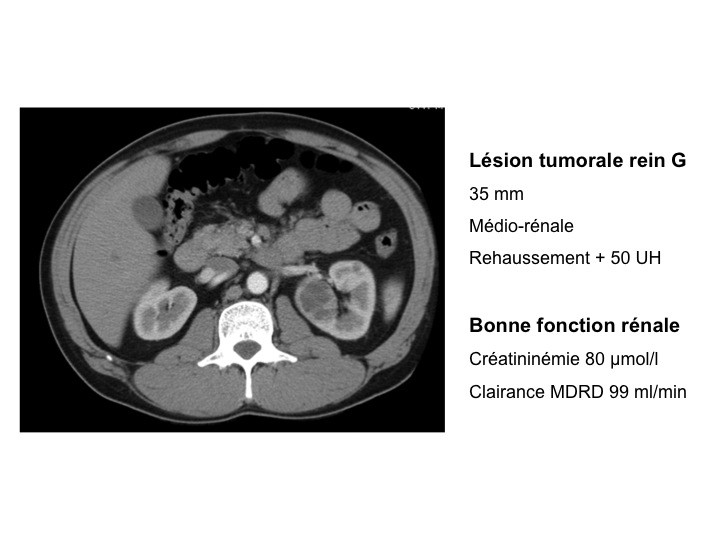

- Définition des petites tumeurs rénales, les recommandations 2010

Jean-Jacques PATARD (Le Kremlin-Bicêtre)